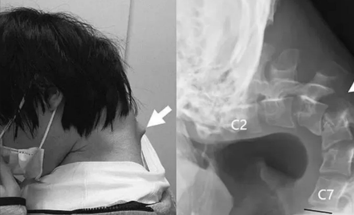

К медикам обратился 25-летний молодой человек, жалующийся на интенсивные боли в области шеи. Он признался, что на протяжении полугода испытывает трудности с поднятием головы. Это привело к проблемам с глотанием, настолько серьезным, что он стал мало есть и заметно похудел.

Во время затворничества он развлекался играми на телефоне. Для удобства просмотра экрана он постоянно наклонял голову, что и стало причиной проблем со здоровьем. Обследование показало, что позвонки его шеи деформировались и сместились, а в позвоночнике образовалась рубцовая ткань.

Изначально врачи пытались помочь пациенту с помощью специального ортопедического воротника, который должен был поддерживать голову в правильном положении. Однако вскоре пациент начал жаловаться на онемение, и воротник пришлось снять.

В результате врачи приняли решение о хирургическом вмешательстве. Сначала хирурги удалили небольшие фрагменты позвонков и часть рубцовой ткани с шеи. Затем в кости были установлены винты и металлические стержни.

Операции прошли успешно. Спустя полгода пациент вновь мог держать голову прямо. Проблемы с глотанием также исчезли. Врачи заключили, что состояние пациента было вызвано сочетанием длительного пребывания в положении с наклоненной головой и скрытым нарушением развития.